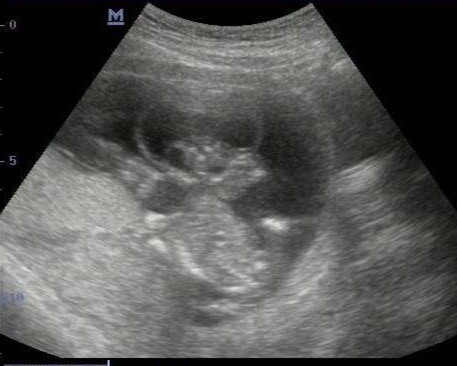

然而,这名孕妇在怀孕30周的时候来看我的门诊,也是一句话,“医生,帮我开个彩超。”做完超声回来,她把检查单给我看,天呐,无脑儿!

这次30周,我接诊的她,超声提示胎儿严重畸形,只能引产。